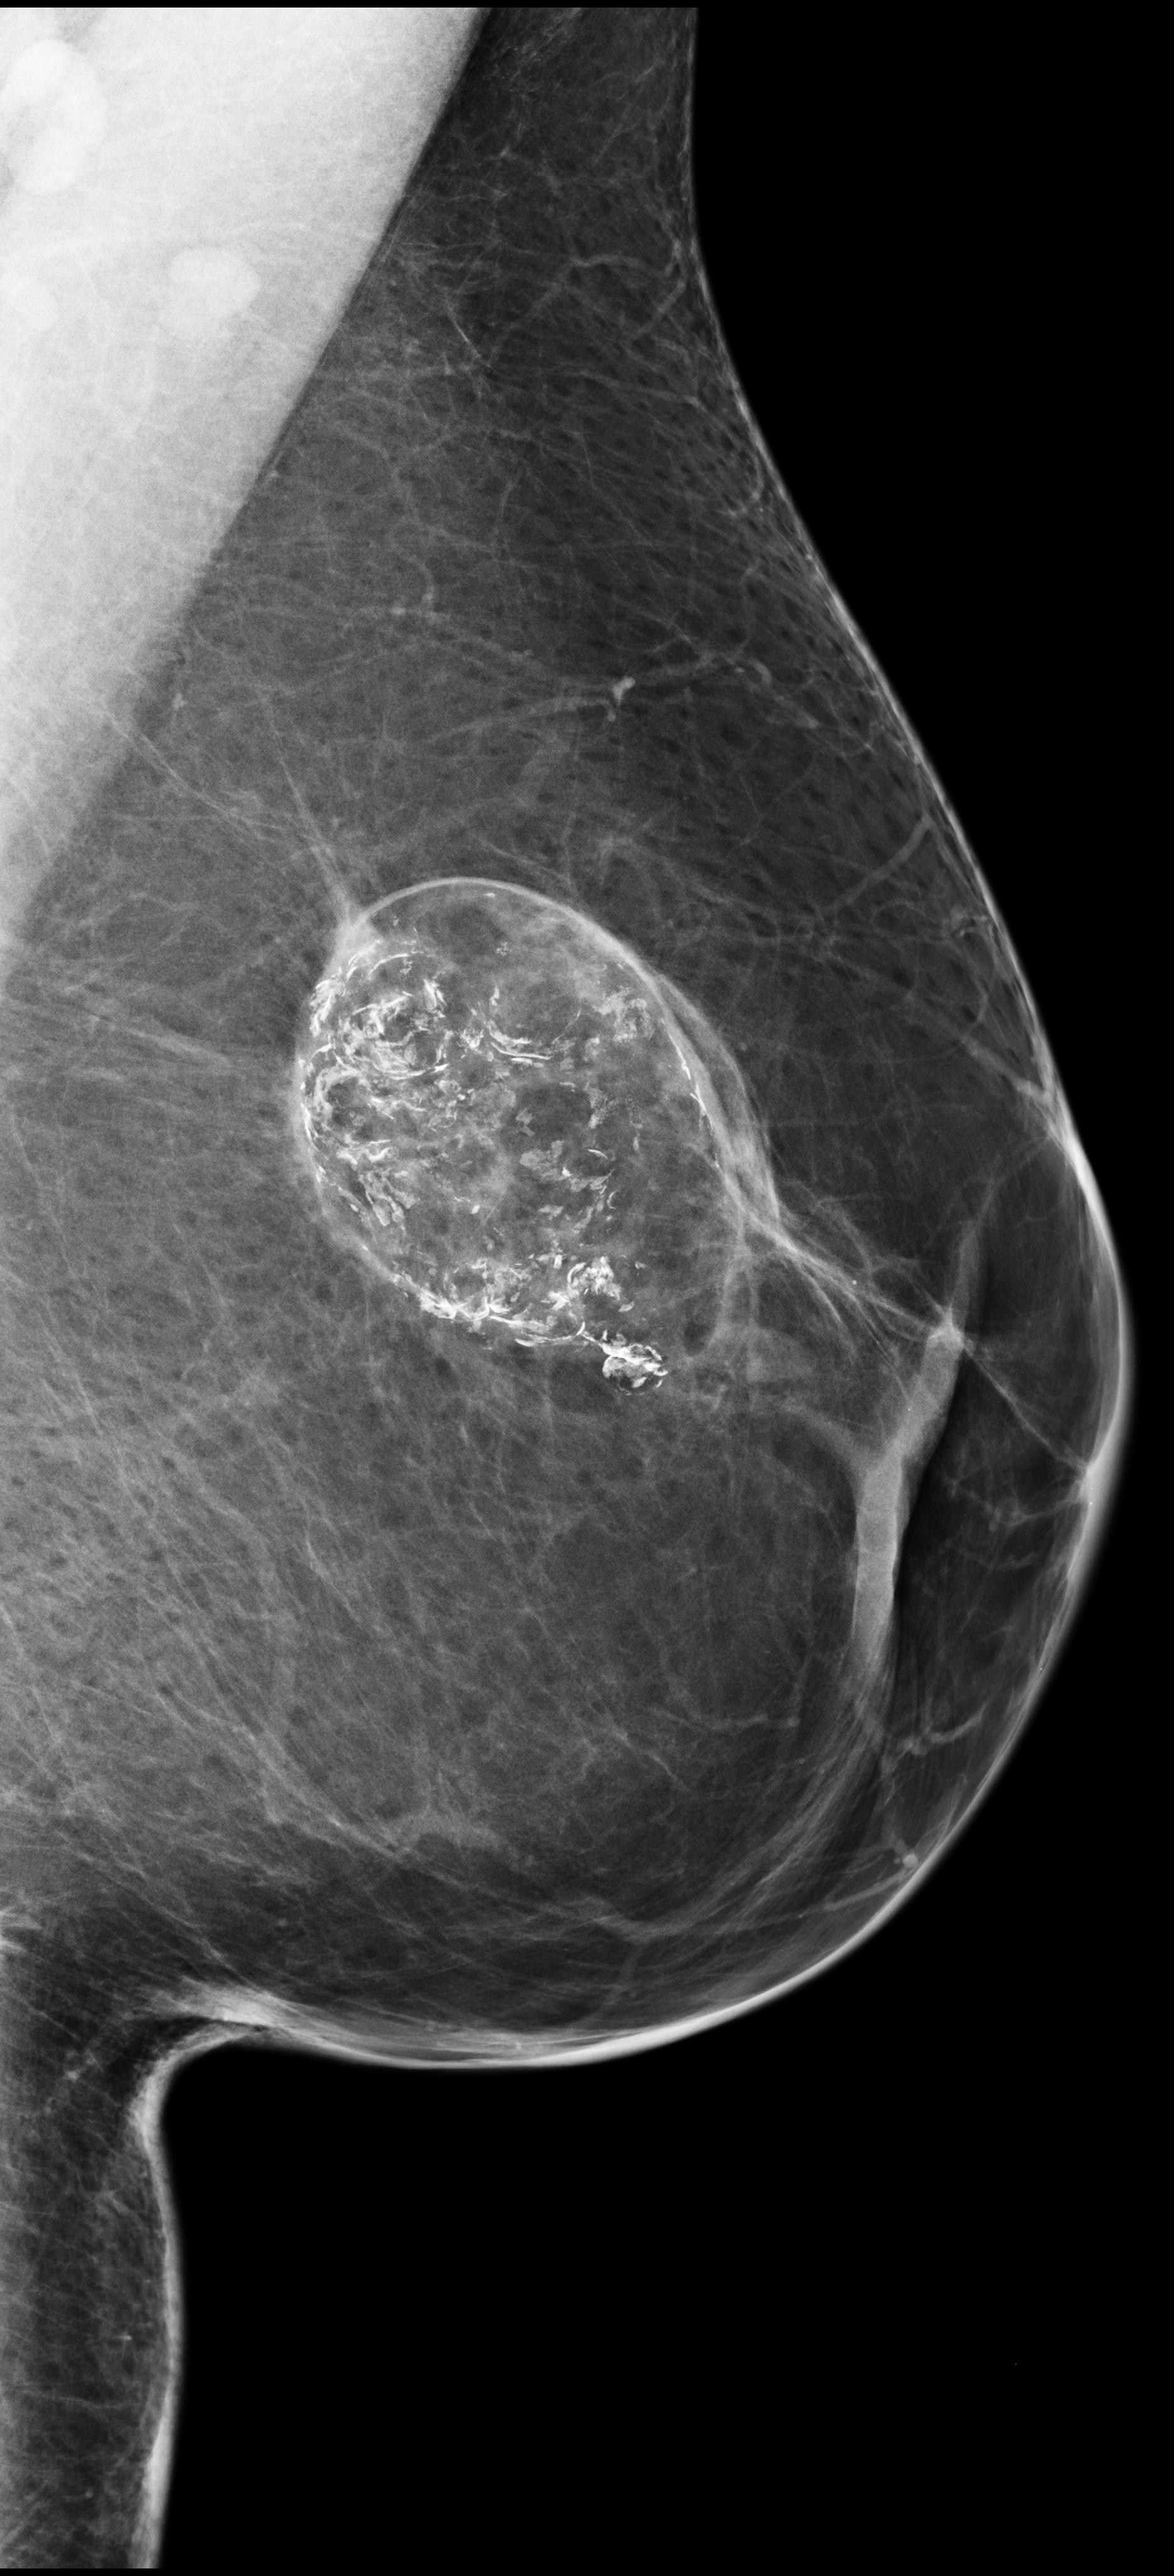

[\capbeside\thisfloatsetupcapbesideposition=left,top,capbesidewidth=6cm]figure[13cm] prior latest highlight prior latest L-CC Refer to caption Refer to caption Refer to caption L-CC Refer to caption Refer to caption L-MLO Refer to caption Refer to caption Refer to caption L-MLO Refer to caption Refer to caption (a) (b)

Figure 3: Test examples where AlignLocalCompare performs better than the single-exam baseline. A breast with a malignant finding shown in (a) (malignant finding is highlighted with red) and one with a benign lesion shown in (b). AlignLocalCompare predicts malignancy with 0.97 probability for (a) and 0.04 for (b), whereas the baseline predicts 0.73 for (a) and 0.24 for (b). There is about a year gap between two exams for both patients.